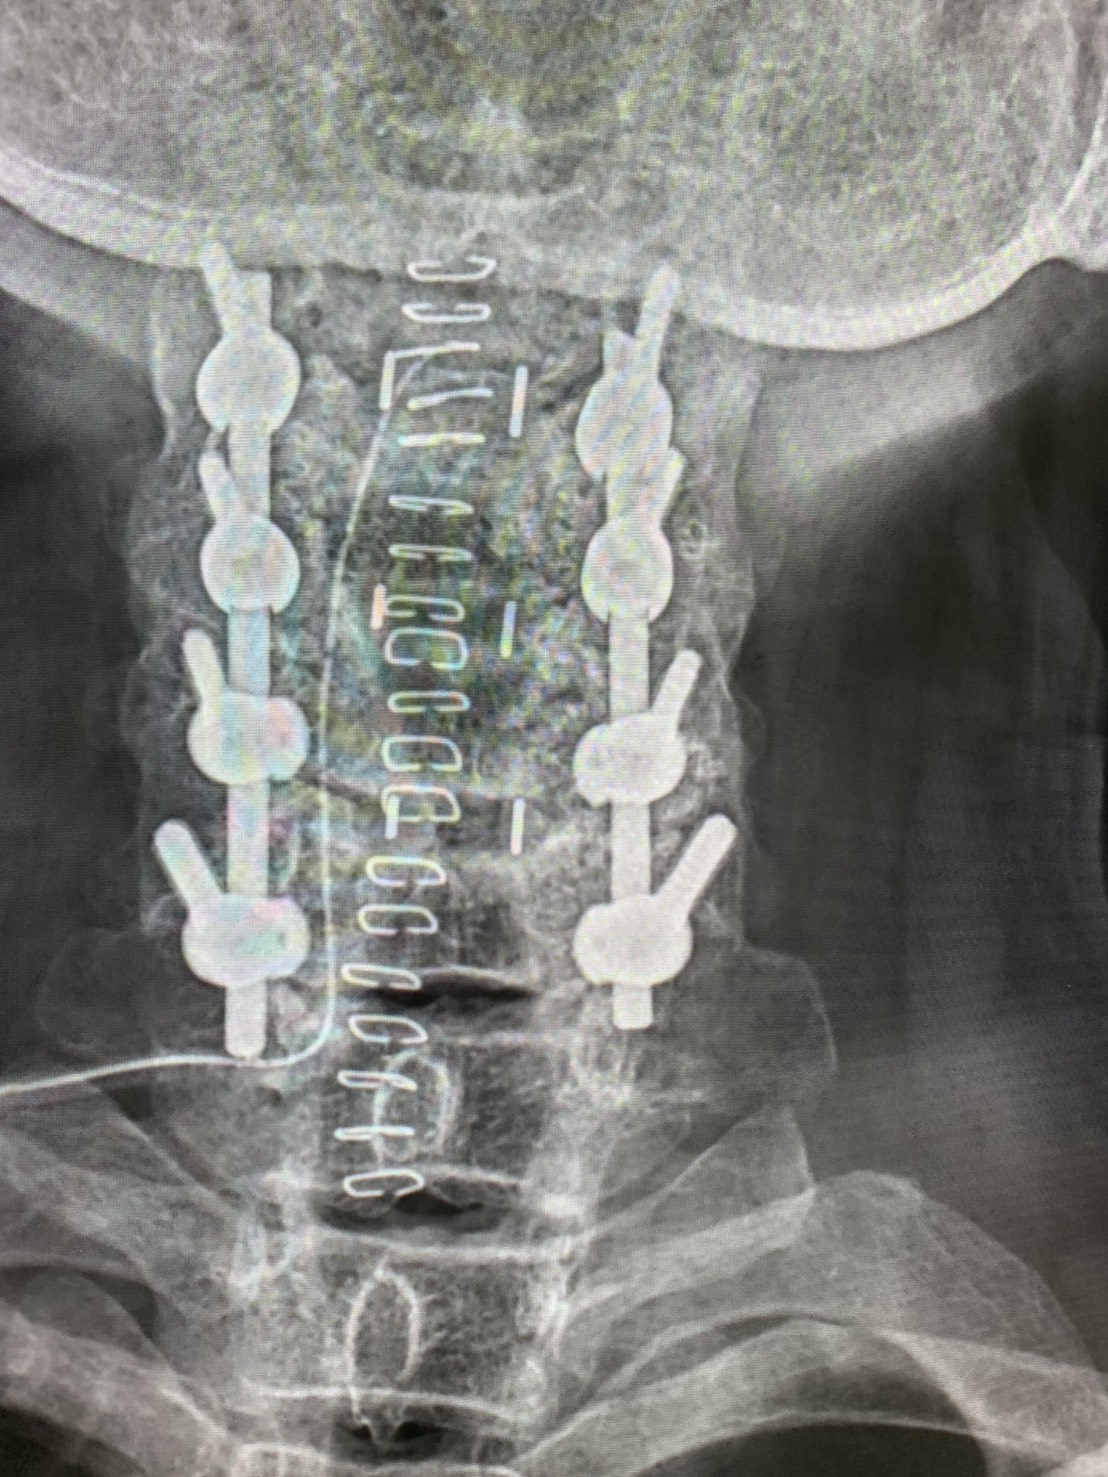

จากภาพ X-ray ในเคสนี้:

ตำแหน่งน็อตและเหล็กอยู่ในระดับดี ไม่พบสกรูหลุดหรือก้านหัก

ปัญหาน่าจะมาจากเนื้อเยื่อรอบ ๆ มากกว่า